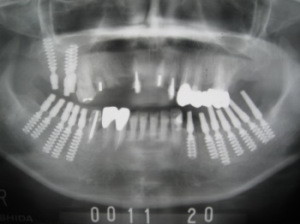

| 2日後、左奥歯にインプラント植立 これで両方の奥歯が噛めるようになりました。 |

| 後日残りの部分にインプラント植立。 これですべての歯が揃いました。 この状態で、骨が固まるまでプラスチックの歯(仮歯)で3〜6か月待ちます。 (抜歯してすぐ植立した前歯のインプラントが一部感染したので、打ち直しをしています。) |